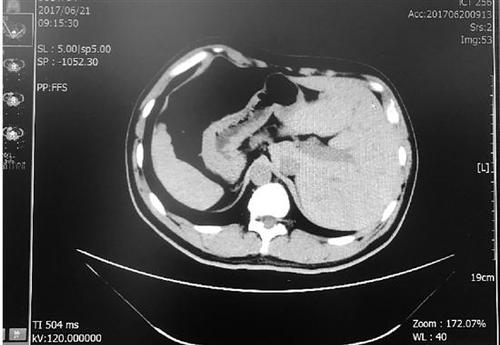

张先生的肝脏在左侧,脾脏在右侧,与正常人相反。

体内的脏器类似于正常人照镜子,五脏六腑的位置与常人相反,过着“颠倒”的人生,这就是我们常说的“镜面人”,发生概率只有百万分之一。

得知需要手术,张先生脱口而出的第一句话就是:“我是个镜面人?!闭庖馕蹲?,他的心、肝、脾等脏器都在与常人相反的位置,肠道也是如此?!耙话闳说拇蟪κ撬呈闭氲?,阑尾在右侧,而镜面人的大肠是逆时针方向,阑尾在左侧?!?/p>

“镜面人是完全性内脏反位的俗称,通常表现为胸腔、腹腔器官及解剖结构的完全左右反位?!甭粢绞樯?,“镜面人”是在人体胚胎发育过程中,只有父母体内基因的一个位点同时突变才会出现,这种突变是隐性遗传,遗传几率很低,发生率约为百万分之一。